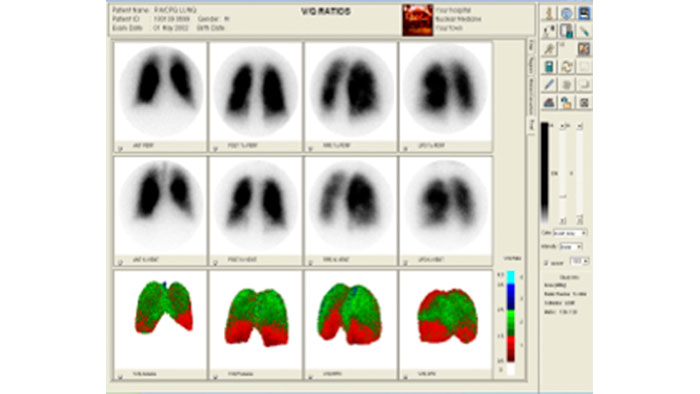

NM JETPack Application Suite

NM JETPack Application Suite for general MI includes a complementary set of organ-specific applications to meet the current and evolving needs of MI users, including endocrine, gastric, hepatobiliary, lung, neuro, renal, and whole-body and bone applications.

Benefits

- Allows calculation of regional cerebral blood flow, brain perfusion index, dopamine transport, liver perfusion, micturition, and gastro-esophageal reflux.

- An optional IDL developers’ kit is available for development of applications.

NM Processing Application Suite

Streamline Molecular Imaging workflow

Offers comprehensive analysis and processing protocols for planar and SPECT studies including renal, lung, whole-body and bone, cardiac (first pass, shunt, and MUGA), gastric, esophageal, hepatobiliary, and endocrine applications.

Benefits

- Features Philips AutoSPECT Pro software for automated SPECT reconstruction and re-orientation.

- A set of tools to perform daily and periodic quality assurance for SPECT Cameras with motion correction, as well as CT-based attenuation and scatter correction.